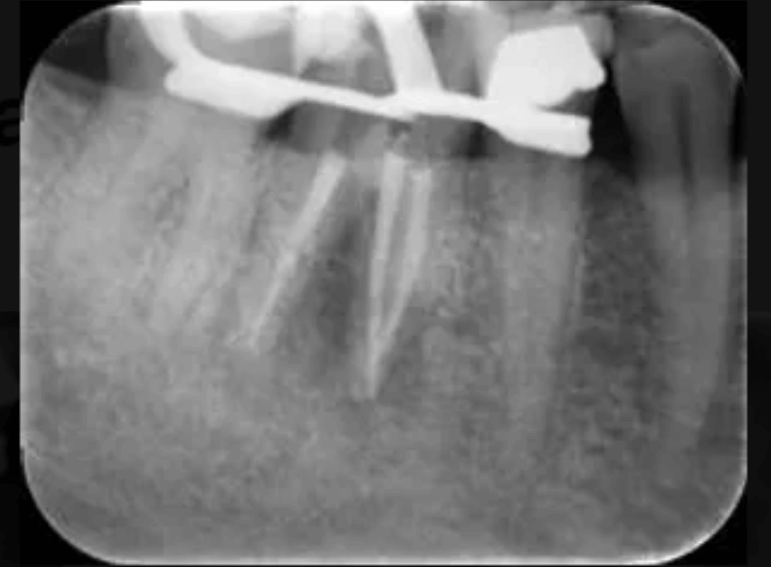

Removal of silver points and endodontic revision of a molar.